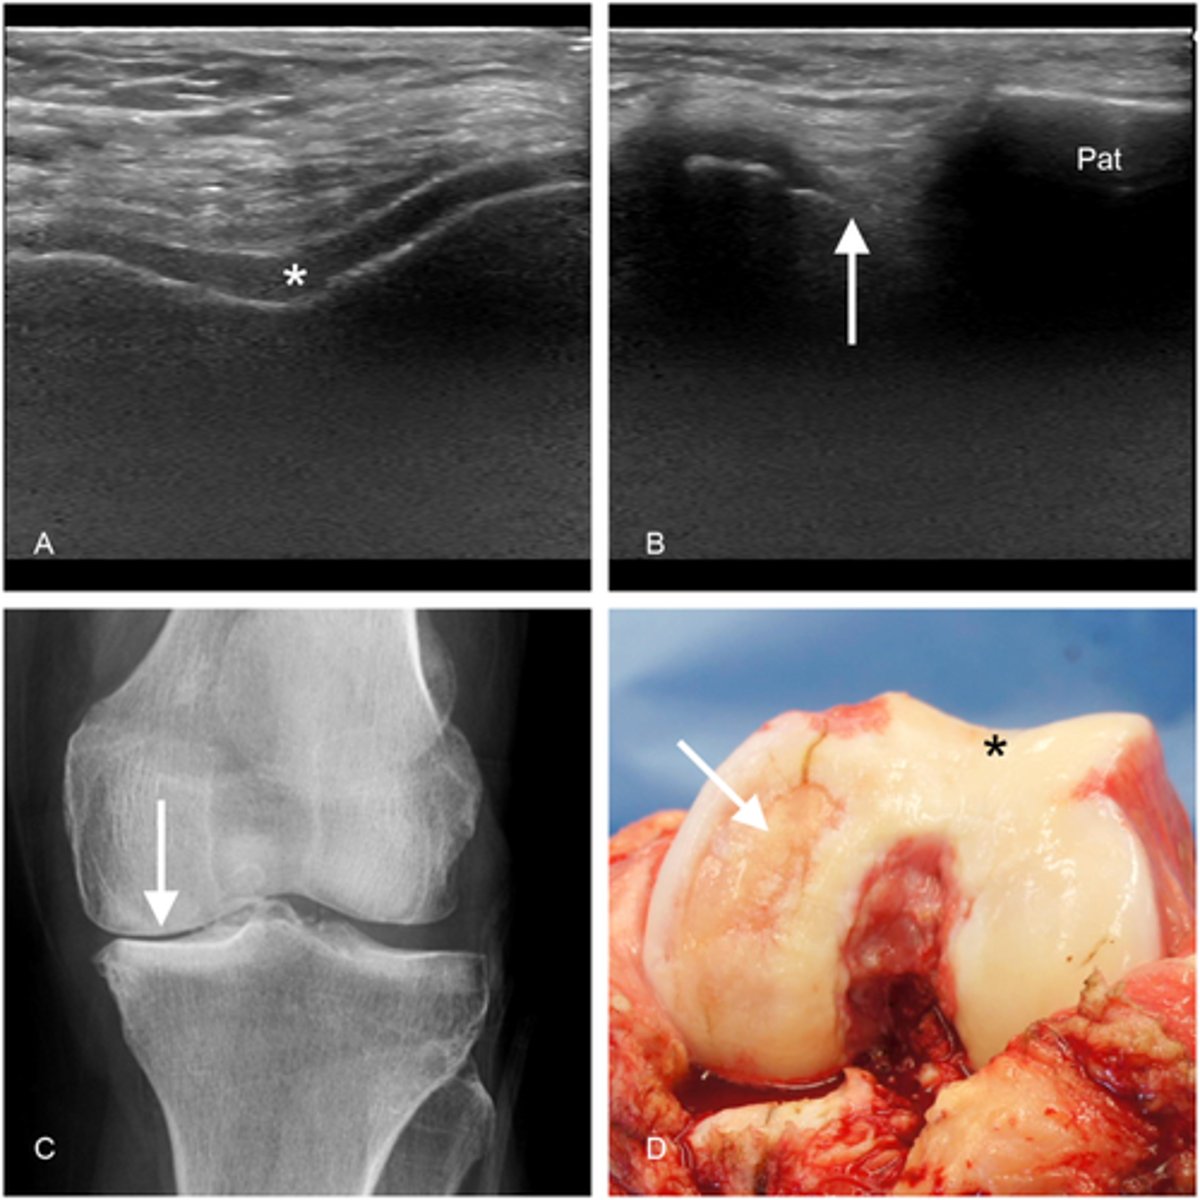

eroding cartilage

cartilage

osteoarthritis (image)

What symptoms can you see on an x-ray?

bone spurs, narrowing space

Why can't cartilage grow back?

it's avascular

radiograph "LOSS"

a. Loss of joint space

b. Osteophytes - spurs of bone

c. Subarticular sclerosis

Increased density of bone on joint line

d. Subchondral cysts

Small fluid filled holes in bone on the joint line